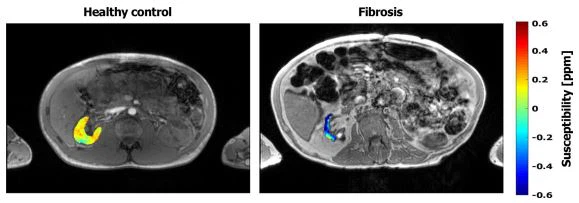

Kuvassa 7 esitetään QSM-kartat, jotka on asetettu suuruuskuvien päälle terveen vapaaehtoisen ja yhden tutkitun potilaan, jolla on munuaisten interstitiaalinen fibroosi. Oikean fibroottisen munuaisen herkkyys oli vahvasti diamagneettinen (− 0,43±0,02 ppm).

Kuva 7 Suuruuskuvat, jotka on peitetty oikean munuaisen QSM-kartan kanssa terveelle vapaaehtoiselle (vasen kuva) ja potilaalle, jolla on munuaisfibroosi (oikea kuva). Fibroottinenmunuainenosoittaa vahvaa diamagneettista arvoa (− {0}},43±− 0,02 ppm), joka oli huomattavasti pienempi kuin terveillä mitattu QSM-arvomunuaistenkudos (oikea munuainen {{0}},04±0,07 ppm)

QSM:n mahdollisen diagnostisen arvon tutkimiseksi potilas, jolla onmunuaistenfibroosi esimerkkinä loppuvaiheen munuaispatologiasta otettiin mukaan tutkimukseen. Aikaisemmin on raportoitu, että munuaisfibroosi lisää munuaiskudoksen diamagneettista sisältöä [13], mikä johtuu luultavasti kollageenin liiallisesta kertymisestä, joka on voimakkaasti diamagneettista [31]. Keskihajonta huomioon ottaen terveen munuaiskudoksen herkkyys vaihtelee nykyisessä tutkimuksessa noin 0. Tutkimuksessamme fibroottinenmunuainenosoitti vahvaa diamagneettista herkkyysarvoa, joka oli huomattavasti pienempi kuin terveellä munuaiskudoksella. Tulevaa tutkimusta suuremmassa potilasryhmässä tarvitaan munuaisten QSM:n tarkan diagnostisen arvon arvioimiseksi (kvantitatiivinen herkkyyskartoitus).